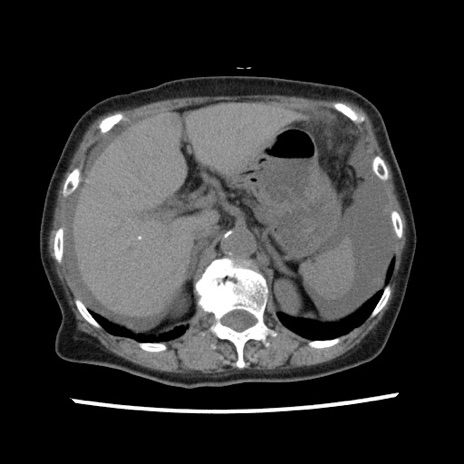

症例1(横断像)

【症例】80歳代女性

【主訴】腹痛

【現病歴】8時間前から腹痛あり来院。

【既往歴】糖尿病、脂質異常症、子宮体癌にて子宮全摘術

【身体所見】意識清明・会話良好だが腹痛で苦悶様、全腹部にわたって反跳痛と圧痛あり

【データ】WBC 13600、CRP 0.14、LDH 224、CK 90